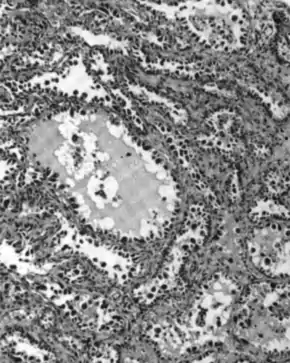

Micrograph of a mucinous ovarian carcinoma stained by H&E | |